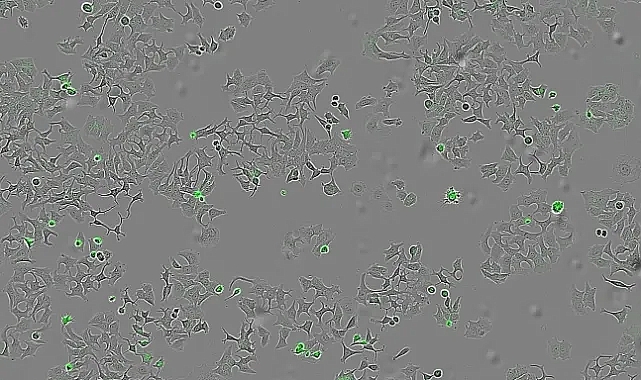

Ekip, HapA proteininin gerçekten kanser hücrelerini öldürüp öldürmediğini test etmek için, HapA üretmeyen 'mutant Vibrio cholerae' türleriyle, sadece HapA üretecek şekilde 'genetik olarak değiştirilmiş bakterilerle' deneyler yaptı.Sonuçta yalnızca HapA proteininin bulunduğu ortamlarda tümör hücrelerinin yaşama oranı azaldı.Araştırmacılar ayrıca, bakterilerin salgıladığı tüm proteinleri içeren bir sıvıyı meme, kolon ve pankreas kanseri hücreleriyle temas ettirdiler.Amaç, HapA proteininin farklı kanser türlerine karşı da etkili olup olmadığını görmekti.Hurtado, “Farklı türlerdeki insan tümör hücrelerinin, bu bakteriyel maddelerle — özellikle HapA ile — temastan sonra hâlâ yaşayıp yaşamadığını ve çoğalıp çoğalamadığını anlamak istedik,” dedi.